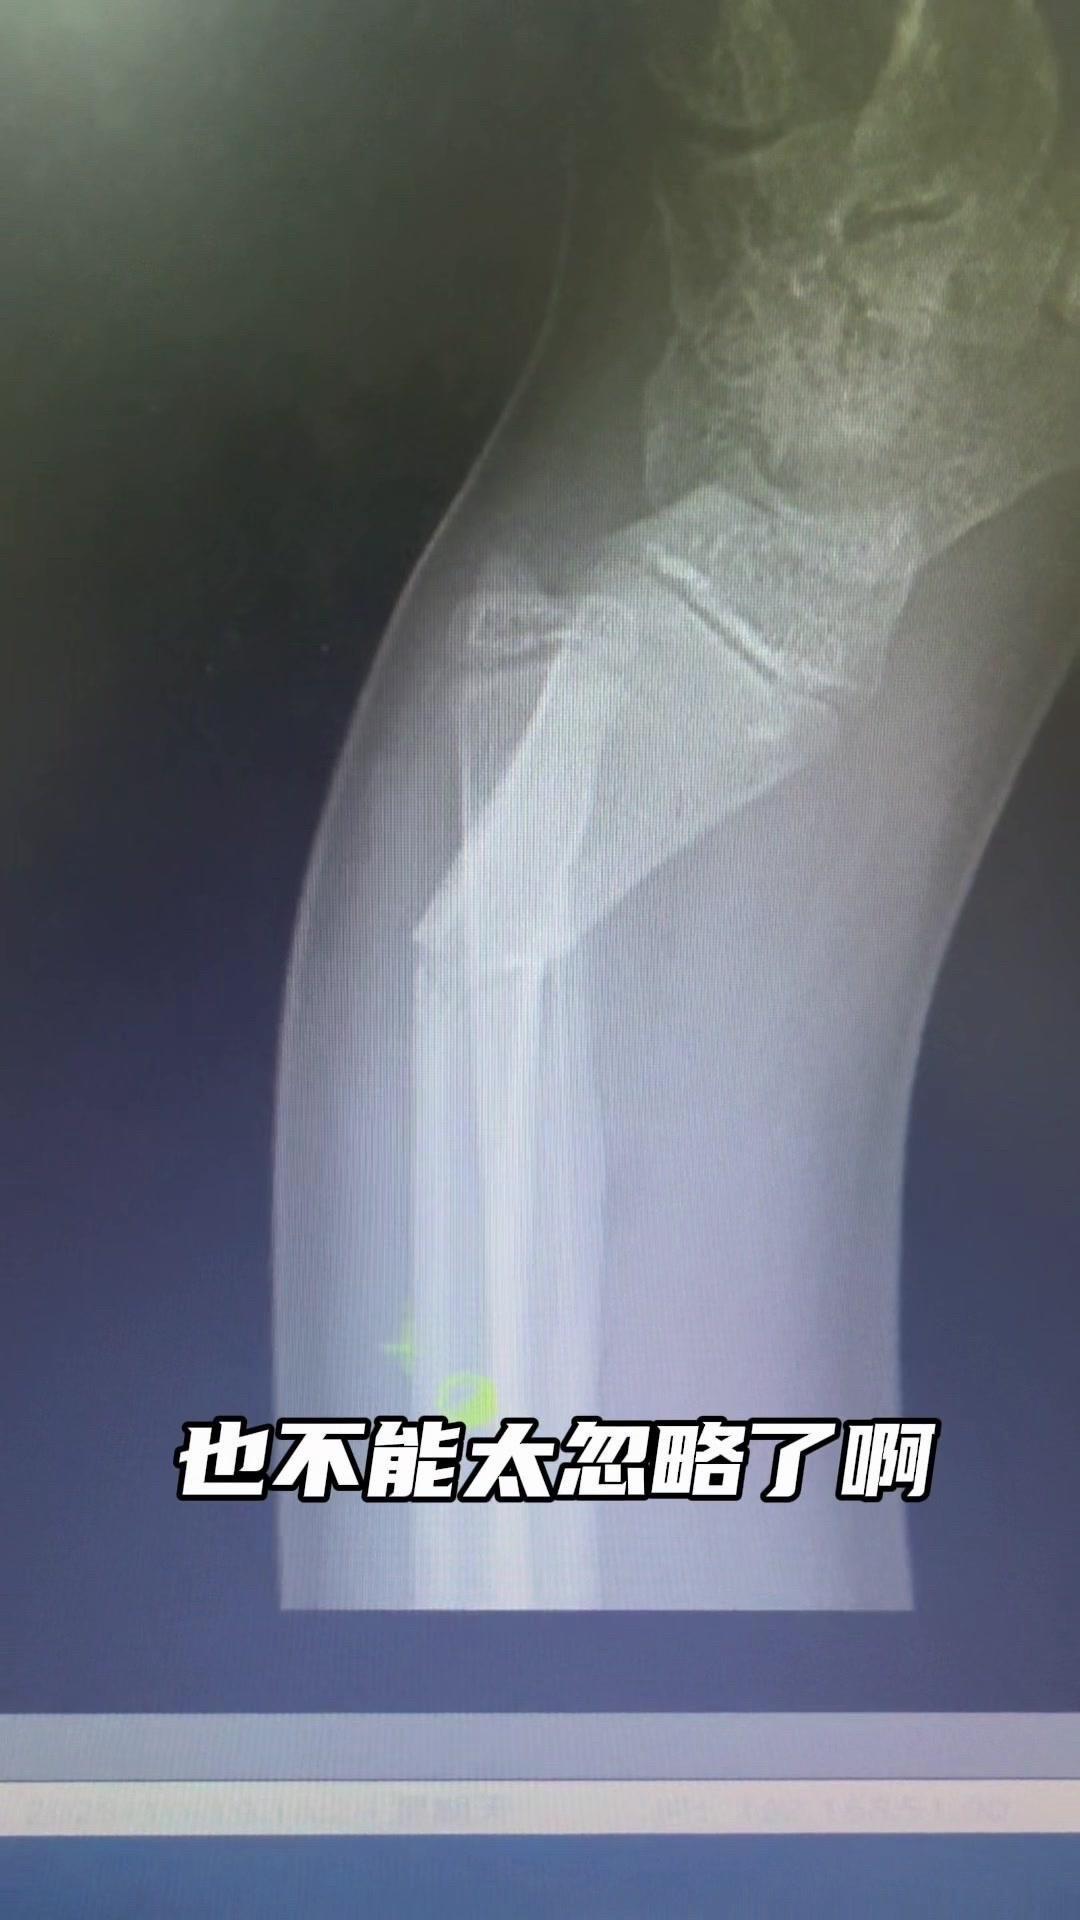

儿童骨折别拖延!💡上周接诊一个10岁女孩,摔了一跤后腕部疼痛还伴有畸形,家长觉得是小伤没在意,结果一周后孩子疼得更厉害,畸形也更明显了。来医院拍片一看,妥妥的骨折,而且才一周就开始出现模糊骨痂,掌区还有45度左右的成角畸形。家长这才意识到问题严重性,其实孩子受伤后出现疼痛、畸形,哪怕看起来不严重,也得及时检查,别让小问题拖成大麻烦。